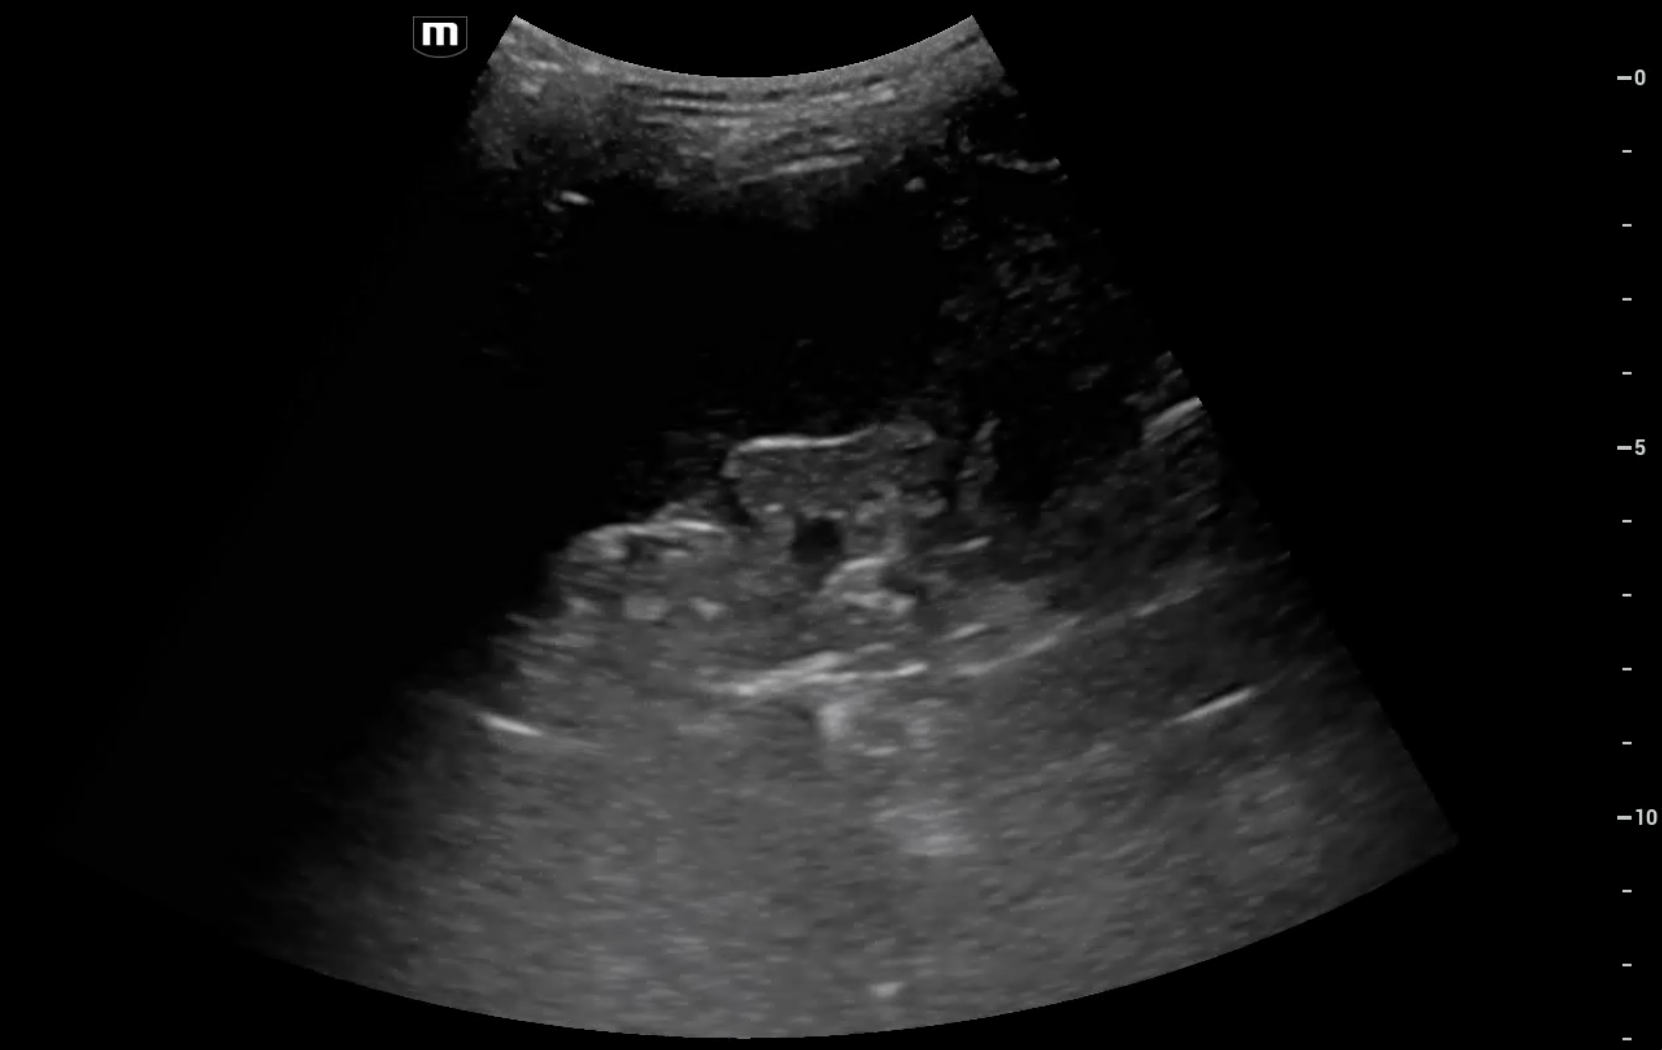

Se completa estudio con ecografía pulmonar a pie de cama, que muestra Sliding conservado, con patrón de líneas B en base y campo medio derecho, con una pequeña consolidación subpleural en base derecha. En base izquierda, consolidación pulmonar, con hepatización, y derrame pleural asociado.